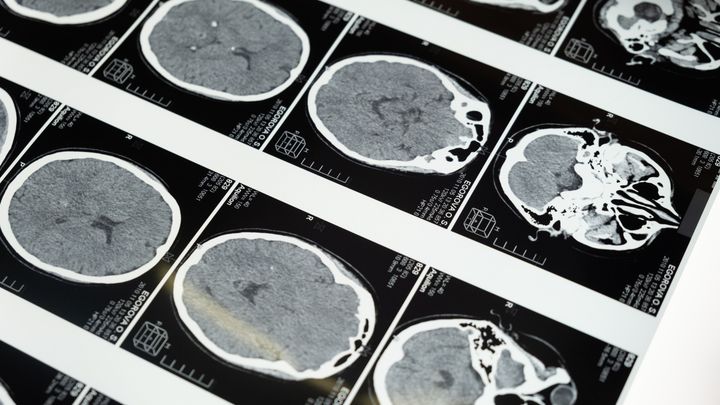

At the Computational Neurogenomics Laboratory, we use genomics, neuroscience, epidemiology, and data science to explore the complexities of the human brain.

Our research investigates the biological factors influencing cognition, behaviour, brain structure, and the risk of neuropsychiatric diseases. By analysing natural DNA variations across populations, we aim to uncover the mechanisms that shape brain function and mental health.

We study a wide range of conditions, including Parkinson’s disease, chronic pain, migraines, self-harm behaviours, depression, and sleep disorders.